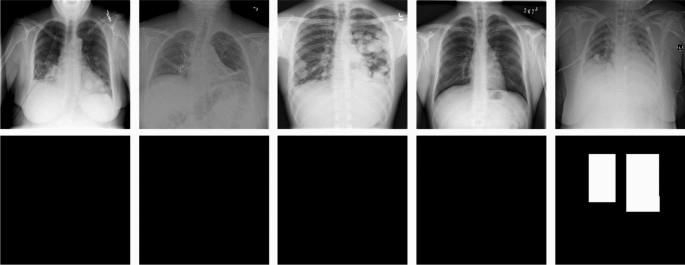

The dataset used for model development and evaluation was obtained from the RSNA Pneumonia Detection Challenge and is part of the ChestX-ray14 dataset, which is publicly available from National Institutes of Health Clinical Center. The dataset consists of the class information, 25,684 frontal-view chest radiographs in Digital Imaging and Communications in Medicine (DICOM) format, and the bounding box information of corresponding labels of different patients. Table 1 lists the demographic characteristics of this dataset, and Fig. 1 presents five examples with class and bounding box descriptions. Figure 2 depicts the CXR images and the corresponding labels of the lung-opacity regions. All frontal chest radiographs were annotated by six board-certified radiologists. Three types of classes were identified in a total of 25,684 images, namely lung opacity (5659 images), normal (8525 images), and no lung opacity or not normal (11,500 images). We randomly selected 24,684 images to form a training set and 458 images for a testing set (lung opacity: 229 images; no lung opacity: 229 images). The data distribution is detailed in Table 1.

Images and labels corresponding to the five examples introduced in the Fig. 1.